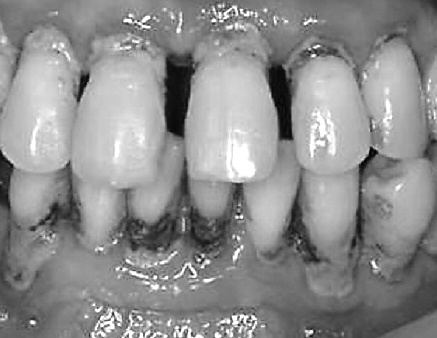

잇몸질환과 치주질환에 탁월한 도움을 주는 성분이 있다.

마그놀롤과 호노키올이라는 페놀성분이 항염과 살균작용을 해주어 입냄새를 제거해 줄 뿐 아니라 충치를 예방해 주는데도 탁월한 효능이 있다.

후박나무 껍질을 물에 달여서 가글하면 치주 병원균을 억제해준다.

잇몸이 자주 붓거나 피가 나고 시린 치주염이 있는 분들의 잇몸질환을 개선시켜주는데 도움을 준다.

국내 유명 제약회사에서 후박나무의 이러한 성분을 연구하고 추출해서 잇몸치료제 개발을 했다.